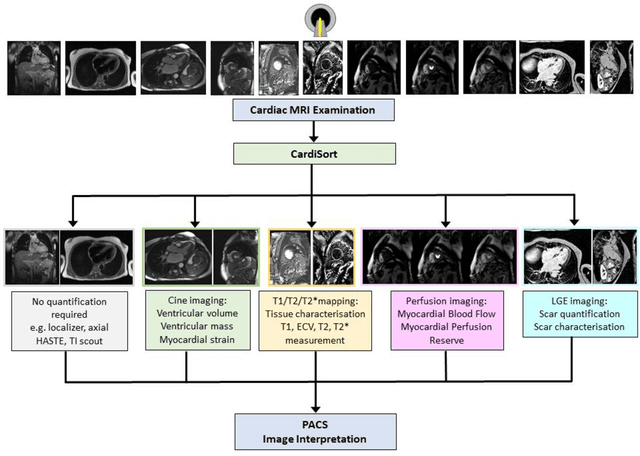

Abstract:Objectives: To develop an image-based automatic deep learning method to classify cardiac MR images by sequence type and imaging plane for improved clinical post-processing efficiency. Methods: Multi-vendor cardiac MRI studies were retrospectively collected from 4 centres and 3 vendors. A two-head convolutional neural network ('CardiSort') was trained to classify 35 sequences by imaging sequence (n=17) and plane (n=10). Single vendor training (SVT) on single centre images (n=234 patients) and multi-vendor training (MVT) with multicentre images (n = 479 patients, 3 centres) was performed. Model accuracy was compared to manual ground truth labels by an expert radiologist on a hold-out test set for both SVT and MVT. External validation of MVT (MVTexternal) was performed on data from 3 previously unseen magnet systems from 2 vendors (n=80 patients). Results: High sequence and plane accuracies were observed for SVT (85.2% and 93.2% respectively), and MVT (96.5% and 98.1% respectively) on the hold-out test set. MVTexternal yielded sequence accuracy of 92.7% and plane accuracy of 93.0%. There was high accuracy for common sequences and conventional cardiac planes. Poor accuracy was observed for underrepresented classes and sequences where there was greater variability in acquisition parameters across centres, such as perfusion imaging. Conclusions: A deep learning network was developed on multivendor data to classify MRI studies into component sequences and planes, with external validation. With refinement, it has potential to improve workflow by enabling automated sequence selection, an important first step in completely automated post-processing pipelines.